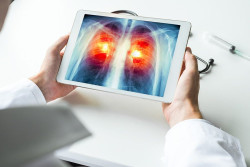

Obtienen nuevos conocimientos sobre la biología de los tumores de pulmón y posibles dianas farmacológicas

Los investigadores han desarrollado el mayor y más completo mapa molecular hasta la fecha del subtipo de cáncer de pulmón carcinoma de células escamosas de pulmón. Su trabajo reúne datos proteómicos, transcriptómicos y genómicos en una visión proteogenómica detallada que ha revelado posibles nuevas dianas farmacológicas, vías de regulación inmunitaria que podrían ayudar al cáncer a evadir las inmunoterapias e incluso un nuevo subtipo molecular, según publican en la revista `Cell`.